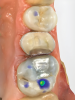

Fig 1 through Fig 5. Single-visit restoration of a maxillary second premolar following root canal treatment. Fig 1: Morphology-guided overlay preparation. Fig 2: IOS bite registration via imaging of buccal tooth surfaces. Fig 3: Preparation margin defined following IOS impression. Fig 4: Overlay design on the IOS platform, integrating adjacent tooth anatomy. Fig 5: Bonded overlay fabricated from CAD/CAM resin-based composite. Fig 6 through Fig 9. Digital workflow for guided endodontics using a digital twin, created by registering an IOI with CBCT data.

Figure 1

Figure 2

Figure 3

IOSs have found extensive applications across various dental specialties.1 In restorative dentistry, they are primarily used for fabricating dental restorations through CAD/CAM workflows, which remains by far their most widespread use (Figure 1 through Figure 5).2 The accuracy of IOSs enables dental professionals to produce restorations with precision that is on par with conventional methods.3 In addition to restorative dentistry, IOSs are being utilized for various applications in prosthodontics, orthodontics, forensic dentistry, and oral and maxillofacial surgery.